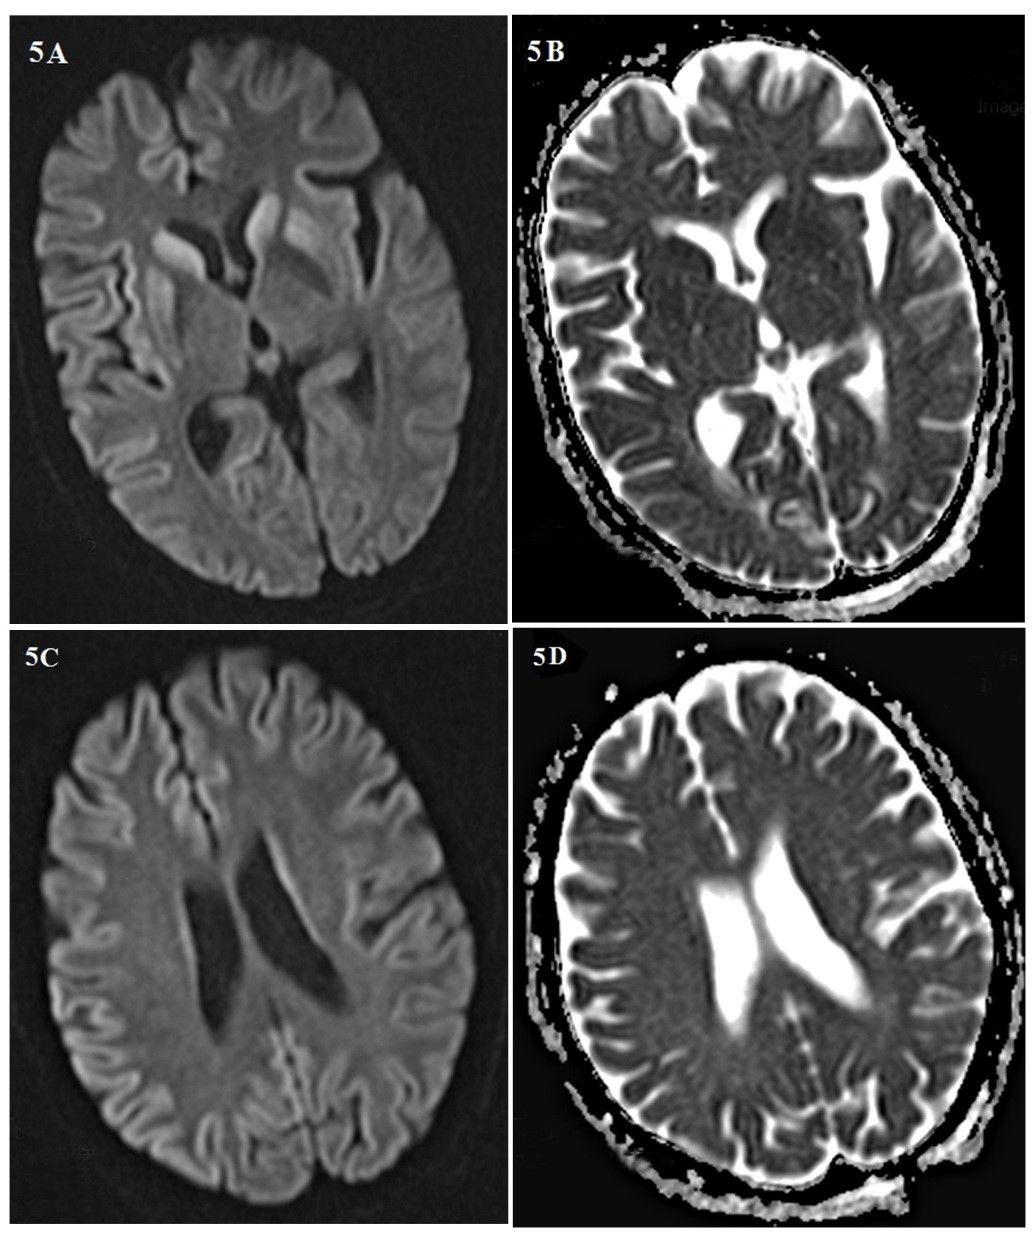

Background: Creutzfeldt-Jakob disease (CJD) is a progressive and fatal prion disease in human and its annual incidence is estimated one per million. Sporadic form of CJD is the most common form of the disease that involved 85% of cases. Case Report: We presented two cases of CJD with the different clinical presentation; a 58-year-old woman who referred with amnesia, depression and a 59-year-old woman with ataxia as her chief complaint. Based on the findings and roled-out the other differential diagnosis, the CJD was confirmed. Both of them died before 12 months after diagnosis. Conclusion: Although CJD is a rare disease with different clinical manifestation, it is considered as one the differential diagnosis of progressive dementia.[GMJ.2019;8:e1357]Â